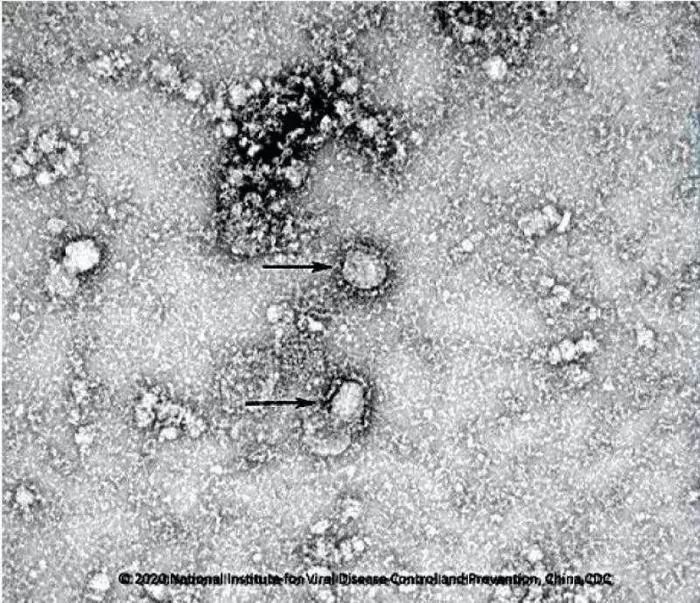

資料圖:新型冠狀病毒武漢株01 圖片來(lái)源:中國(guó)疾控中心網(wǎng)